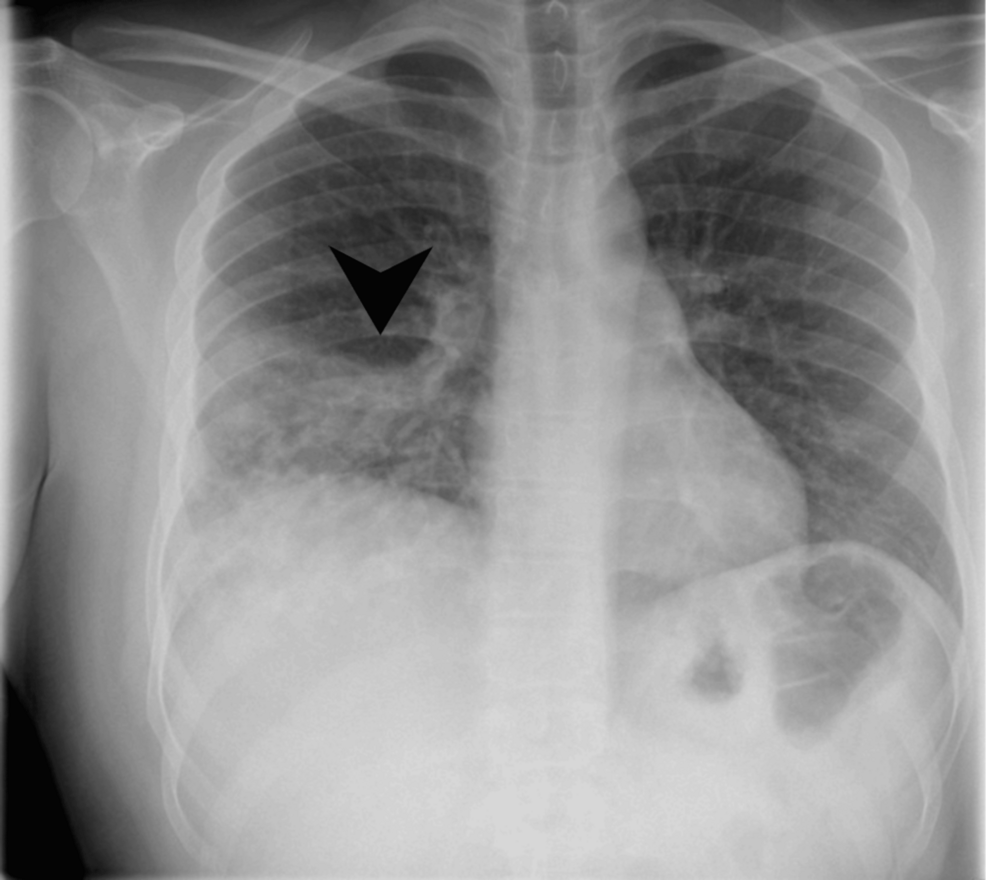

A recent medical report details an extraordinarily rare case involving a healthy young adult who developed a Rasmussen’s aneurysm. This unusual complication was further compounded by a co-infection with a fungal pathogen, alongside tuberculosis.

The case highlights the complex interplay of infections and their potential to manifest in unexpected ways. Tuberculosis, a bacterial disease primarily affecting the lungs, is known for its diverse clinical presentations. Tho, its association with arterial inflammation leading to aneurysms, especially in a young, or else healthy individual, is highly uncommon.

Adding another layer of complexity, the presence of a fungal co-infection alongside tuberculosis suggests a compromised immune state or a particularly aggressive form of disease. Fungal infections,when they occur concurrently with bacterial infections like tuberculosis,can significantly complicate diagnosis and treatment.